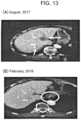

FIG.12 is a graph showing the levels of tumor markers (CA19-9 and CEA) in the blood measured with time before and after alkalinization (pH7.0 or more) of urine by administration of sodium bicarbonate and administration of Opdivo (registered trademark) to a male patient (91 years old) diagnosed with Stage IV advanced gastric cancer associated with multiple liver metastases and lung metastasis.

FIG.13 shows photographs of CT images of the liver before and after alkalinization (pH7.0 or more) of urine by administration of sodium bicarbonate and administration of Opdivo (registered trademark) to a male patient (91 years old) diagnosed with Stage IV advanced gastric cancer associated with multiple liver metastasis and lung metastasis: (A) shows liver metastases of gastric cancer before sodium bicarbonate and Opdivo (registered trademark) were administered (sites indicated by the arrows); and (B) disappearance of liver metastases of gastric cancer after sodium bicarbonate and Opdivo (registered trademark) were administered (site enclosed by a circle indicates a primary lesion (gastroesophageal junction).

A patient (male, 91 years old) was diagnosed, in January 2017, with advanced gastric cancer (Stage IV (associated with multiple liver metastases and lung metastasis)) having a primary lesion in the gastroesophageal junction. A standard therapy in Japan for advanced recurrent gastric cancer, SOX therapy (TS-1 (trade name) (combination drug of tegafur/gimeracil/oteracil potassium) 120 mg/individual, 14daily administration 14 day off; Elplat (trade name) (oxaliplatin) 170 mg, once per 3 weeks) was started from the middle of February, 2017. However, due to severe fatigue, the dose of TS-1 was reduced to 100 mg/individual in the middle and the therapy was continued. Nevertheless, no shrinkage of the primary lesion was observed; on the contrary, the number of metastatic cancers increased in the liver and enlarged (FIG.13 (A)). In addition, the levels of tumor markers, CA19-9 and CEA, continuously increased (FIG.12).

Then, the SOX therapy was stopped from November 2017 and a urinary alkalinization therapy including daily oral administration of 5 tablets of Mylan (trade name) (sodium bicarbonate tablets, 500 mg)×2 times/day, was initiated; at the same time, Opdivo (trade name) (nivolumab) was administered in a dose of 3 mg/kg (body weight) at the intervals of 2 weeks.

As a result, it was confirmed that the urine pH value was alkalinized and was maintained at pH7 to 7.5. It was also confirmed that the blood level of a tumor marker, CEA, decreased from 70.3 ng/mL (November, 2017) to 4.3 ng/mL (March, 2018) and the blood level of CA19-9 decreased from 2,584,107 U/mL (November, 2017) to 29 U/mL (March, 2018) (FIG.12). It was further confirmed that a primary lesion gastric cancer in the gastroesophageal junction and a number of metastatic cancers to the liver disappeared (FIG.13 (B)). The urinary alkalinization therapy has been continued and development of another cancer and recurrence/metastasis have not been confirmed.

Generally, the five year survival rate of an advanced and/or an end-stage gastric cancer patient (70's, male, Stage III) is reported as about 7.1% even though the rate slightly varies depending on the application or non-application of, e.g., a chemotherapy; and the median overall survival of gastric cancer patients (gastroesophageal junction cancer) treated with Opdivo (trade name) was reported as about 5.26 months (Lancet. 2017 Dec. 2; 390 (10111): 2461-2471). The advanced and/or end-stage gastric cancer is still an untreatable disease having no effective therapy, at present. Administration of Opdivo (trade name) contributes to extending a life of a patient with end-stage gastric cancer; however, tumor shrinkage and a decrease of a tumor marker level were seldom confirmed. Nevertheless, in the patient mentioned above, development of another cancer and recurrence/metastasis have not been confirmed up to present. The result is unpredictable from common technical knowledge on disease condition and survival period of general advanced and/or end-stage gastric cancer patients and regarded as an extraordinary effect, i.e., a therapeutic effect and remission effect, based on administration of a urinary alkalinization agent according to the present invention.